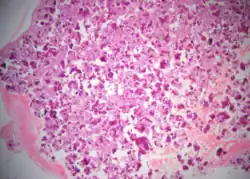

Cemento-ossifying fibroma is a well-demarcated lesion, often encapsulated by a thin fibrous capsule and sharply separated from adjacent normal bone. It shows significant internal variation, with differing amounts of fibrous and mineralized tissue—even within the same lesion. Mineralization is often more prominent centrally and typically includes osteoid, woven to lamellar bone, and dense basophilic cementum-like calcifications. Bony trabeculae may fuse into broad sheets or form thick, anastomosing strands. Osteoblastic rimming is commonly seen around bone trabeculae.[27]

The stroma is fibroblastic and may exhibit areas of hypercellularity and nuclear hyperchromasia; however, mitotic activity is rare and cellular atypia is minimal .[28] The mineralized component may include acellular or paucicellular cementum-like spheres along with bone structures .[28]

Though rare, hemorrhagic cystic degeneration—resembling aneurysmal bone cyst formation—can occur, more commonly in juvenile variants.[27][29] Histological overlap can exist among subtypes: psammomatoid and trabecular JOF may exhibit features resembling COF, and vice versa. In syndromic cases, such as gnathodiaphyseal dysplasia, COF lesions appear more fibrous with basophilic, acellular bone droplets and spherical ossicles, but histologically resemble nonsyndromic counterparts .[30]

Histologically, COF comprises a fibrocellular stroma with varying degrees of ossification, including trabecular or lamellar bone and cementum-like material.[35] Differentiation from other fibro-osseous lesions—such as fibrous dysplasia and cemento-ossifying fibroma—requires histopathological assessment.[36]